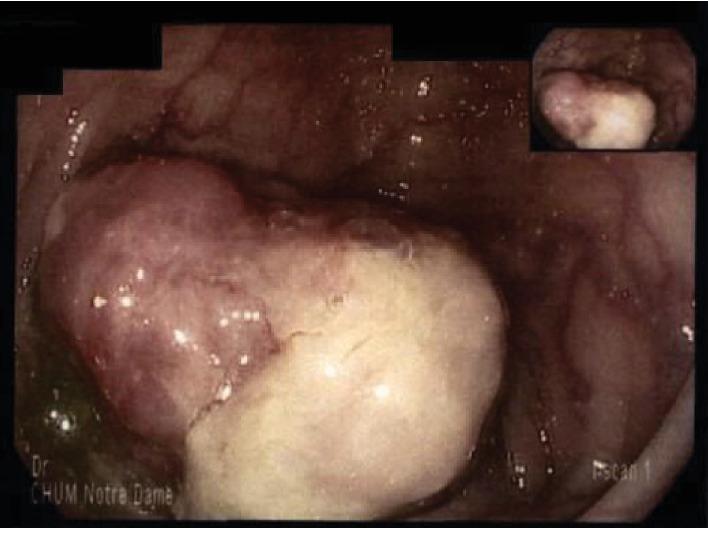

Primary colorectal leiomyosarcoma is an excessively rare entity. It is associated with an aggressive behavior and typically favor hematogenous spread. The current standard of care is surgical resection. A 49-year-old patient presented with a 2-month history of fever. A PET-scan revealed a hypermetabolic mass in the transverse colon, and colonoscopy confirmed a tumor. A right hemicolectomy was performed. Histopathological diagnosis was of a leiomyosarcoma. Fourteen months after the surgery, a follow-up abdominal scan revealed a 2 cm mesenteric lymph node that was hypermetabolic on PET-scan. The mesenteric lymph node was resected and histopathology confirmed a leiomyosarcoma metastasis. This case opens the controversy on the management of rare lymph node recurrences in colorectal leiomyosarcoma.

原发性结直肠平滑肌肉瘤是一种极其罕见的疾病。它具有侵袭性,通常倾向于血行转移。目前的标准治疗方法是手术切除。一名49岁患者有2个月的发热病史。PET扫描显示横结肠有一个高代谢肿块,结肠镜检查证实为肿瘤。进行了右半结肠切除术。组织病理学诊断为平滑肌肉瘤。手术后14个月,腹部随访扫描显示一个2厘米的肠系膜淋巴结,PET扫描显示其代谢活跃。切除该肠系膜淋巴结,组织病理学证实为平滑肌肉瘤转移。该病例引发了关于结直肠平滑肌肉瘤罕见淋巴结复发治疗的争议。